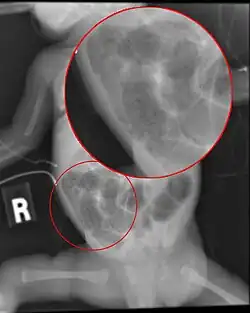

Symptomen kunnen zijn: verminderde voedselopname, een opgeblazen buikje, verminderde activiteit, bloed in de ontlasting, braken van gal, afsterven van de darmen en multi-orgaanfalen. Bij premature baby's die minder dan ongeveer 1400 gram wegen, ontwikkelt 5 tot 7 procent NEC en sterft 15 tot 25 procent daarvan eraan.[1]